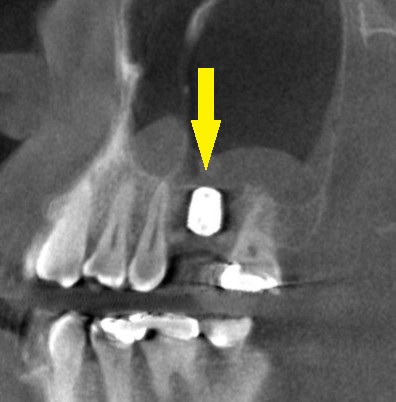

下の写真、3段目が手術後のCTで、上方の上顎洞という空洞の粘膜を少し持ち上げるようにして、インプラントを埋入しました。